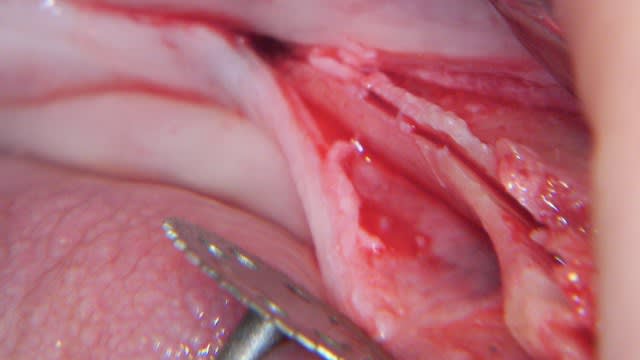

comme cela ?

photo reçue, pud de formation implanto

Exactement Ceramik .

C'est plus facile en haut qu'en bas ( os + élastique)

C'est plus facile sur de grandes étendues que sur unitaire ( + idem que pour un lambeau, meilleur lasticité)

J'utilise piezo pour la première tranchée puis ciseaux à os pour amorcer le clivage

et je termine par foret de 2 mm plus osteotome à frapper ou expanseur de Mis

Parfois un coup de foret terminal ou plus petit selon le site et le cas

Parfois décharges osseuse mesial distal et parfois ( en bas) amorce du pliage apicale

Comme dit pavx il faut prendre son temps et "sentir" l'os